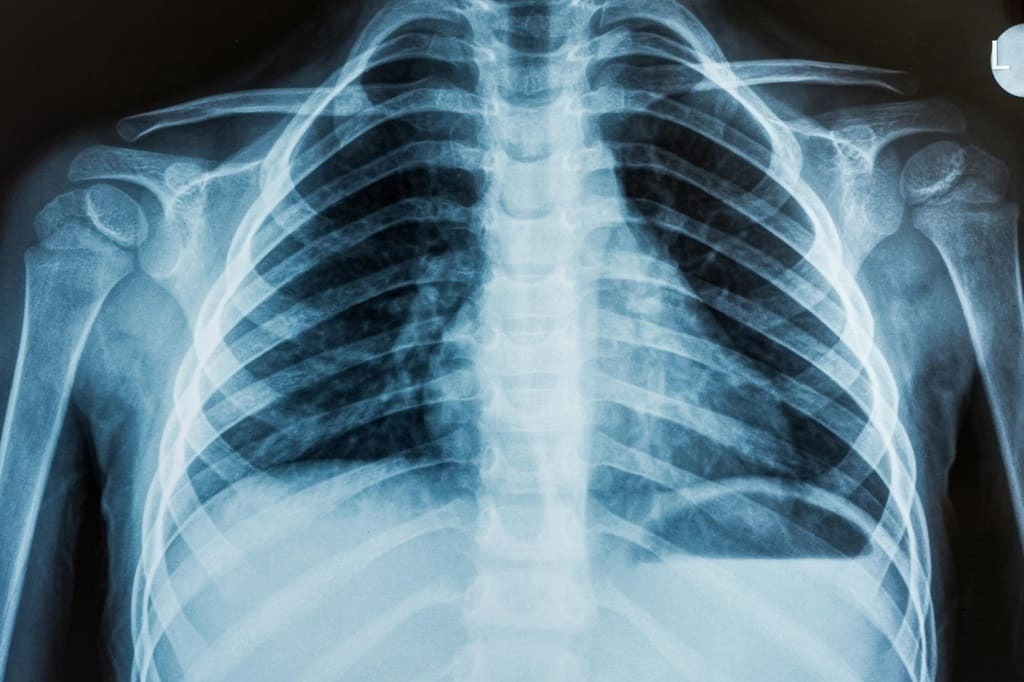

ایکسری

۸ نوامبر ۱۸۹۵ میلادی برابر با 18 آبان ۱۲۷۴ خورشیدی ویلهلم کُنراد رونتگِن به کشف پدیدهای نائل شد که علم پزشکی را بهطرز شگفتآوری دگرگون کرد. این کشف که تماشای درون بدن را میسر کرد پرتو ایکس بود. رونتگن زمانیکه در دانشگاه وورتسبرگ استاد بود طی آزمایشی که در آن، لامپ کروکز (Crookes tube) را در کاغذ سیاهی پیچیده بود، دید که پرده آغشته به یک ماده فلوئورسنت که در نزدیکی لوله قرار داشت، بیدلیل درخشید. او با تکرار چندباره این آزمایش نتیجه گرفت که این درخشندگی اسرارآمیز از کاتد نمیآید، بلکه برآمده از صفحه آلومنیوم یا آنُد است. بدین ترتیب او پرتوی را کشف کرد که معلوم نبود چیست و ازاینرو، آن را پرتو ایکس نامید. پساز مطالعات بیشتر، او در اول ژانویه ۱۸۹۶ نسخههایی از دستنوشتهها و چند عکس گرفتهشده با پرتو ایکس را برای چند فیزیکدان و دوستان مشهوری در گلاسگو و پاریس ازجمله لرد کلوین فرستاد و بهاینترتیب، دانشمندان دیگر را از کشف این پرتو جدید آگاه کرد.